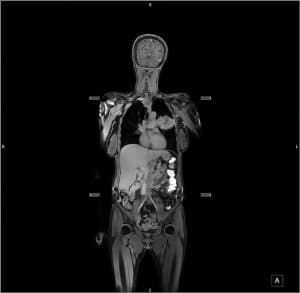

在评估癌症的蔓延方面,全身MRI比多次扫描更有效

对于斯图尔特泰勒教授,位于伦敦大学医院大学,医生真正需要加快这个过程是一种单尺寸适合的方法。考虑到这一点,泰勒教授和他的团队建立了两项临床试验,以测试全身MRI扫描是否会对传统过程有任何好处,以检测癌症在整个身体中的蔓延量。

这些临床试验由NIHR卫生技术评估项目资助,涉及近500名被诊断为肺癌(187名患者)或结直肠癌(299名患者)的患者。这是迄今为止进行的规模最大的全身MRI扫描(简称WB-MRI)前瞻性试验,涉及英格兰各地16家不同的医院。

结果表明,WB-MRI方法与患有肺癌或结肠直肠癌的患者的多种扫描方法以及多种扫描方法。特别是,它同样擅长发现疾病传播。事实上,对于几乎每个患者,医生表示他们将根据惯常扫描基于WB-MRI建议同样的治疗。即使在12个月之后,初始WB-MRI结果也仍然是准确的准确,以决定最好的治疗作为多次扫描的标准方法。

对大多数病人来说,一次全身扫描就足以确定最佳治疗方案。不到7%的结直肠癌患者和不到20%的肺癌患者需要进一步检查以补充WB-MRI。因此,使用WB-MRI作为一次性检查的想法确实有效。